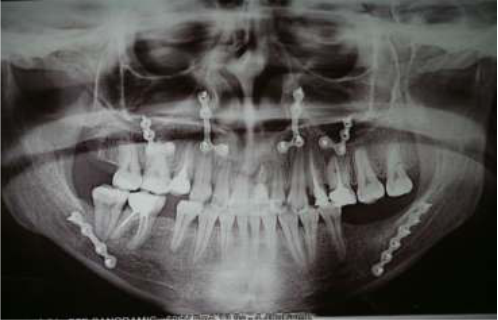

Полный цифровой протокол установки имплантата и немедленная нагрузка

Установка имплантатов и немедленная не окклюзионная нагрузка.

Полный цифровой протокол установки имплантата и немедленная нагрузка.